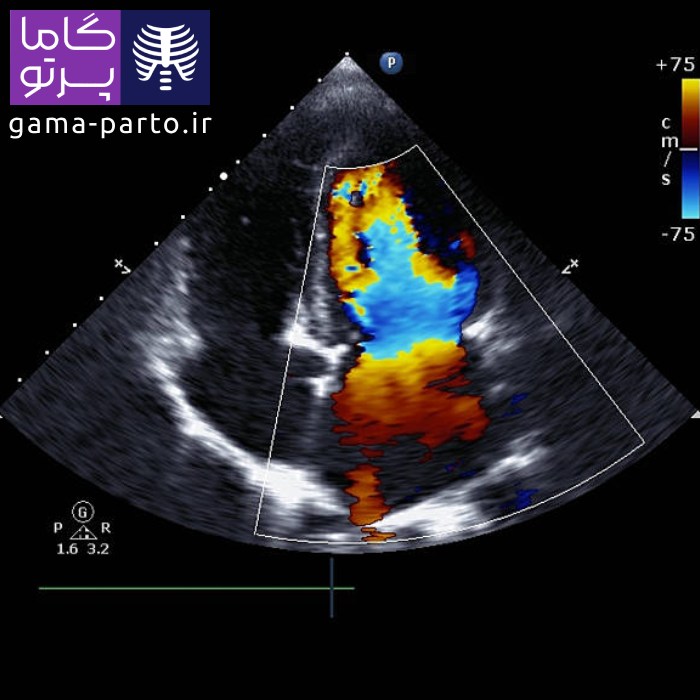

اکو قلب داپلر رنگی - Color Doppler Echocardiography

در تکنیک داپلر رنگی، دادههای مربوط به اندازه و شکل قلب (بهصورت دوبعدی) با اطلاعات داپلر طیفی ترکیب میشوند تا سرعت و جهت جریان خون با رنگهای مختلف نمایش داده شود. بهطور نمونه، رنگ قرمز نشاندهنده حرکت خون به سمت پروب است. این کدگذاری رنگی باعث میشود متخصص قلب بتواند بهسرعت اختلالات احتمالی را شناسایی کند. شایان ذکر است کیفیت تصاویر این روش در دستگاههای قابل حمل گاما پرتو بسیار بالا بوده و برای تشخیص دقیق مورد استفاده قرار میگیرد.